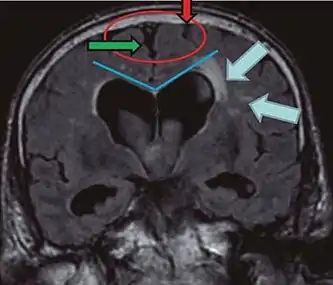

- Imaging from magnetic resonance imaging (MRI) or computed tomography (CT) is needed to demonstrate enlarged ventricles and no macroscopic obstruction to cerebrospinal fluid flow. Imaging should show an enlargement to at least one of the temporal horns of lateral ventricles, and impingement against the falx cerebri resulting in a callosal angle ≤ 90° on the coronal view, showing evidence of altered brain water content, or normal active flow (which is referred to as "flow void") at the cerebral aqueduct and fourth ventricle.

| CSF spaces over the convexity near the vertex (red ellipse | Narrowed convexity ("tight convexity") as well as medial cisterns | Widened vertex (red arrow) and medial cisterns (green arrow) |

| Callosal angle (blue V) | Acute angle | Obtuse angle |

| Most likely cause of leucoaraiosis (periventricular signal alterations, blue arrows |

Transependymal cerebrospinal fluid diapedesis | Vascular encephalopathy, in this case suggested by unilateral occurrence |